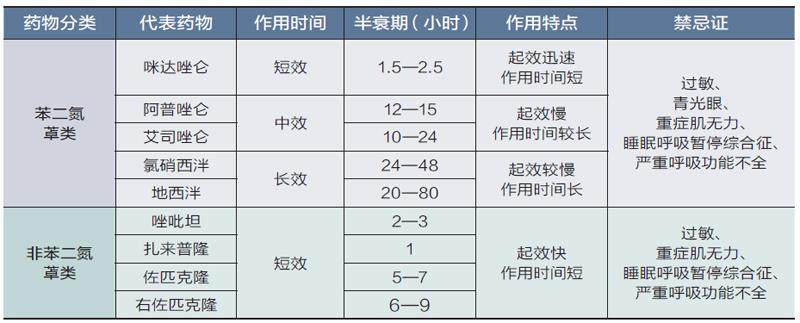

防病强身 | 安眠药不是“洪水猛兽”,但也别乱用

防病强身 | 安眠药不是“洪水猛兽”,但也别乱用